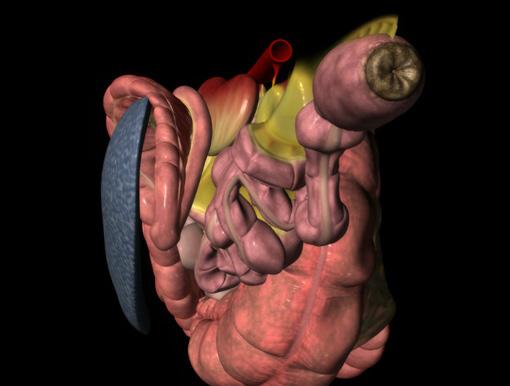

76 Reduce recurring entrapment colic

Jackie Bellamy-Zions talks to Dr. Nicola Cribb about new research showing how preventative surgery can reduce the risk of recurrent nephrosplenic entrapment colic in horses.

THE KING CHARLES III STAKES (5f ) | £700,000